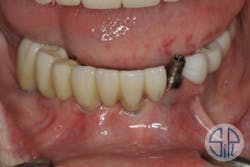

A full-arch restoration on transmucosal abutments was planned. A rigid resin pattern, open-tray, implant level impression was taken (figure 1). The laboratory provided the dentist with straight, transmucosal abutments (figure 2) and a verification jig that was used to verify occlusion, phonetics, and esthetics (figure 3).

Figure 1: Rigid resin pattern, open-tray, implant level impression